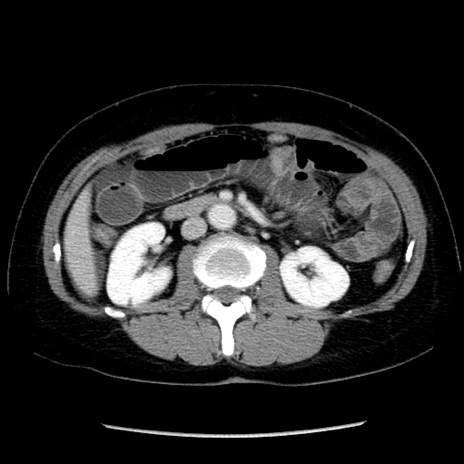

症例6(横断像)

【症例】50歳代女性

【主訴】下腹部痛

【現病歴】本日朝より下痢2回あり。 昼食を食べた後、嘔吐3回、下腹部痛認め、症状軽快せず、当院救急搬送。

【既往歴】卵巣癌術後(8年前に当院で卵巣摘出)

【身体所見】 意識清明、腹部:平坦、腸蠕動音→、やや硬、下腹部自発痛・圧痛あり、反跳痛あり、筋性防御なし。

【データ】WBC 16000、CRP 0.01